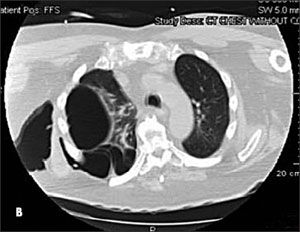

A chest radiograph showed herniation of a large right lung bulla through the intercostal space into the chest wall (A). This was confirmed on a CT scan of the thorax (B) with coronal reconstruction (C). His left lung was normal.

The herniation presents as a chest wall mass that may be asymptomatic or associated with pain or dyspnea. The mass is noncrepitant, which distinguishes it from subcutaneous emphysema and herniated lung parenchyma. Its dimensions change with the respiratory cycle: increasing with inspiration and decreasing with expiration. The hernia is usually easily reducible.

The diagnosis is readily made by imaging. CT provides additional information about the state of the underlying lung and orifice of the hernia.